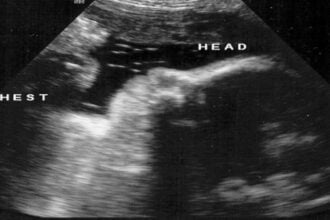

17. haftayı tamamlayan bebeklerde cilt altında bulunan yağ depoları artık dolmaya başlar. Yağ depolarının dolması bebeğin hızla geliştiğinin göstergesidir. Bebeğin gelişimine bağlı olarak anne adayında da kilo artışı oluşur. Bu dönemde plasenta ve bebeğin boyutu yaklaşık olarak aynı oranlardadır. Bebekte bu dönemde dolaşım ve solunum sistemleri tam anlamıyla çalışmaya başlar. Bu dönemde bebeğin kalbi devamlı kan pompalamaktadır. Bebeğin kalbi bir günde ortalama 30 litre civarında kan pompalamaktadır. Anne karnındaki bebeğin artık emme, yutkunma ve göz refleksleri bu dönemde ortaya çıkmaktadır. Bebeğin içinde yer aldığı amniyon sıvısını bebek içine doğru çekmekte ve geri dışarı bırakmaktadır. Bu durum bebeğin doğumdan sonra doğal nefes alış verişi için gerekli bir sistemdir. 17. hafta da bebeğin kilosu 150 gramdır. boyu ise 18 cm. dir.